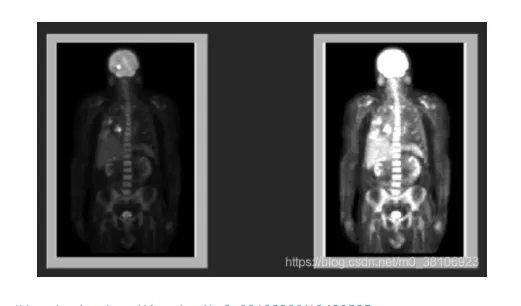

接下来使用乘法运算增强人体骨骼图像,原图像中的人体骨骼很难看清,有必要将图像和一个常量相乘以扩展其灰度级,从而增强图像的亮度和对比度。程序设计思路如下所示:

程序先为图像读取分配了缓冲区Src,并从文件PET.tif中读入灰度图像数据。

为了避免乘法运算过程中数据溢出,程序将读入的灰度图像类型从U8转换为I16,并且分配了I16类型的缓冲区以保存计算结果。

IMAQ Multiply将I16类型的源图像与常量4相乘,将其灰度级放大4倍。

此后再由IMAQ Cast lmage将计算结果转换为U8类型并显示在图像控件中。

程序结束前释放所有分配的缓冲区。由程序运行结果可以看出,倍乘后的图像明显比原图像易于观察。

效果如下所示: